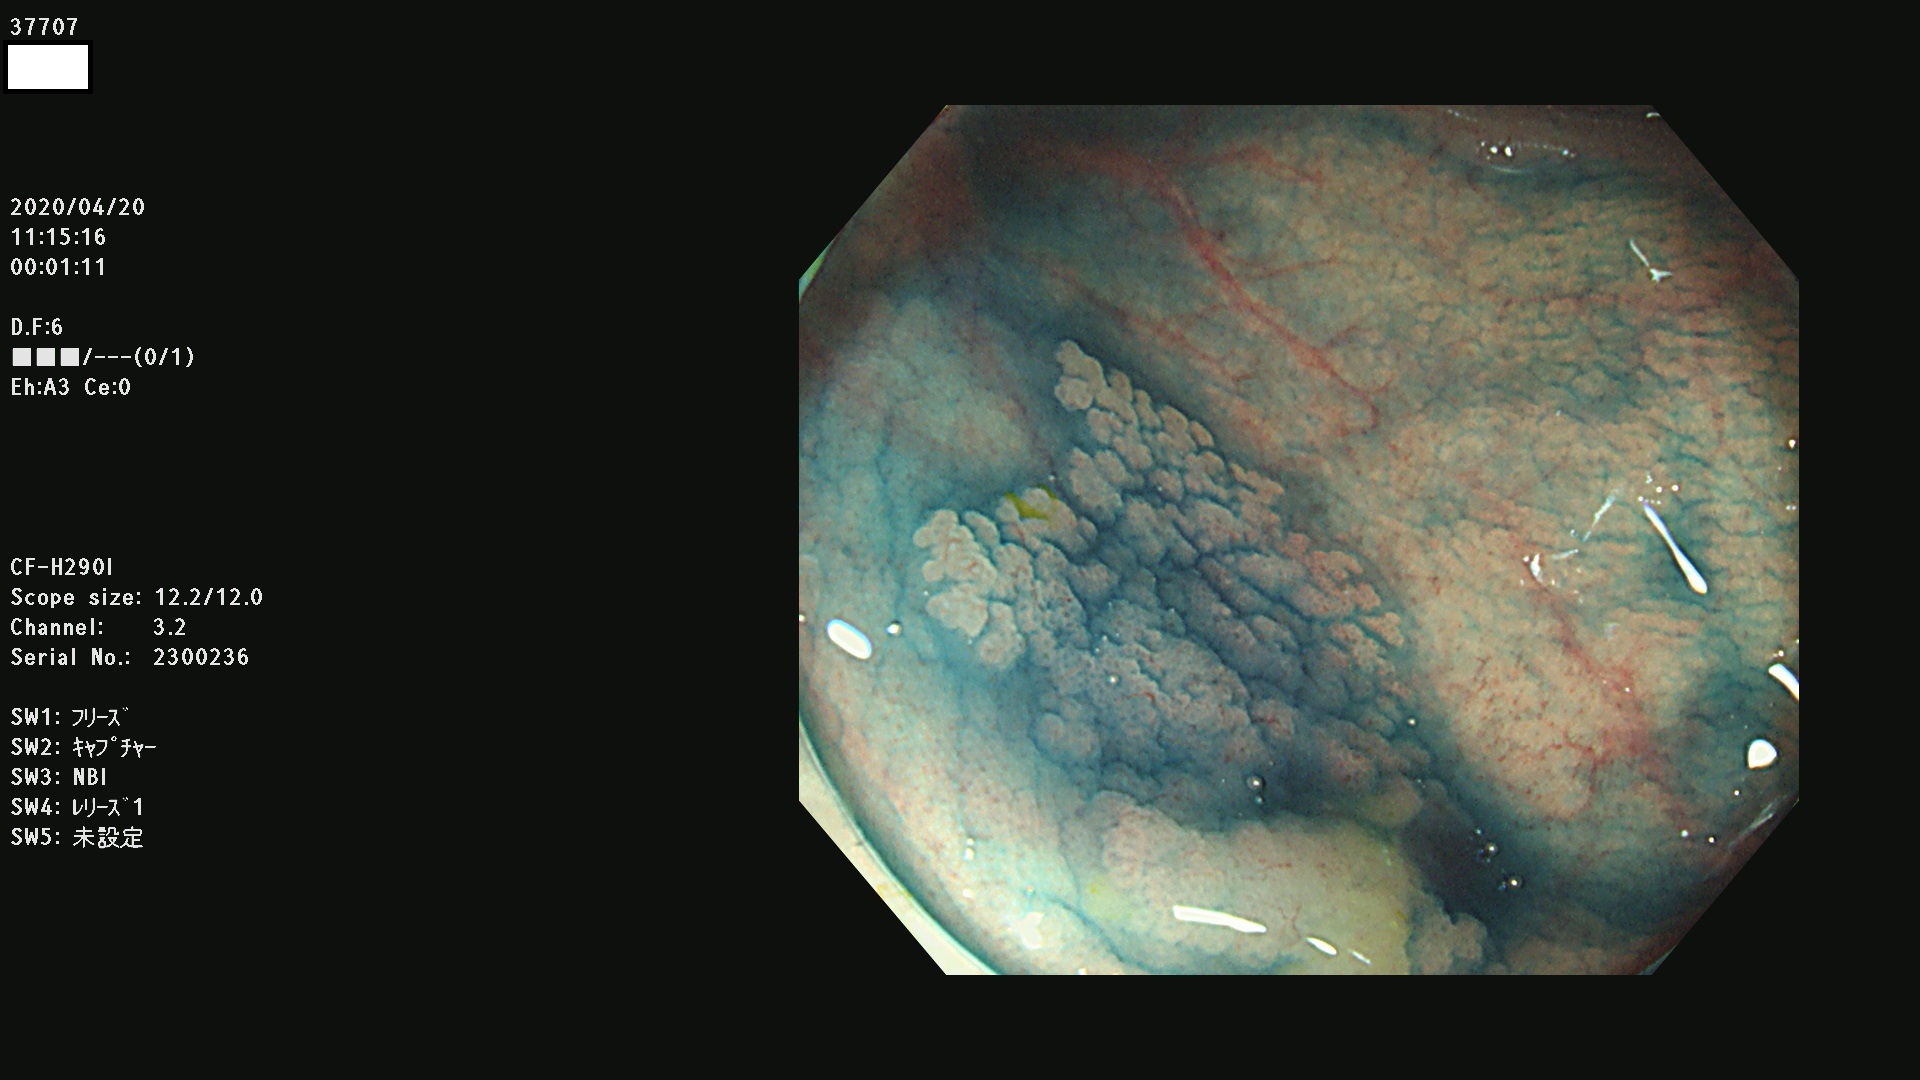

37700 37701 37702 37703 37704 37705 37706 37707(SSAPのみ) 37709 37711 37712 37715 37716 37717 37720 37722(SSAPのみ) 37724 37725 37726 37727 37728 37729 37731 37732 37733 37736(SSAPのみ) 37737 37739 37740 37741 37742 37744 37745 37748 37749 37750 37751 37752(SSAPのみ) 37753 37754 37755 37757 37758 37760 37761 37762(SSAPのみ) 37763 37764 37765 37766 37767 37768 37769 37771 37772 37774 37775 37776 37777 37780 37781 37782 37783 37784 37785 37787(SSAPのみ) 37788 37791 37792 37793 37794 37795 37799

発見困難で危険性の高い平坦型病変(上記100名より抽出)